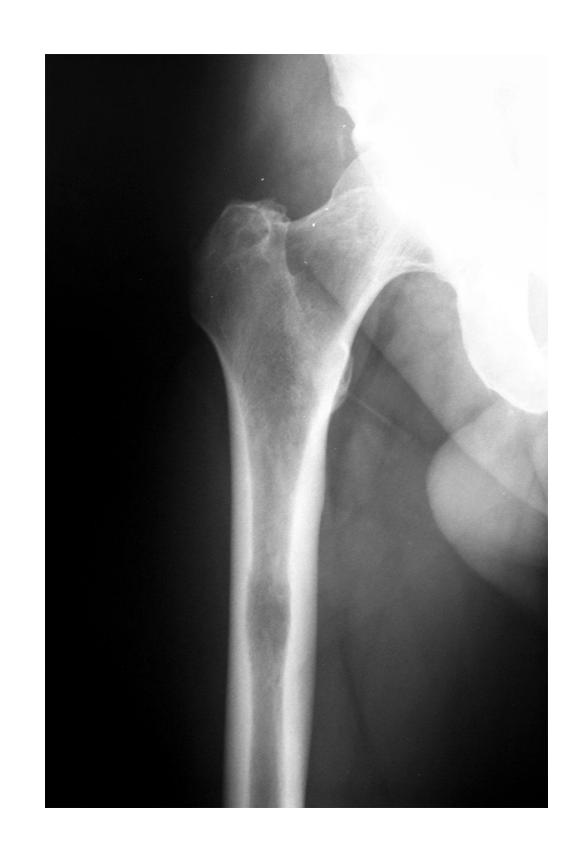

A 50-year-old male tripped over the edge of carpet at home. He heard a crack and is unable to walk. He gave history of progressive weight loss. On clinical examination, he was in pain with a deformity at upper right thigh. He looks pale.

What are the key x-ray findings?

- Decreased bone density in the right proximal femur

- Fracture in the neck of the femur

- AP view of the right proximal femur

What is the diagnosis?

- Pathological fracture due to osteoporosis